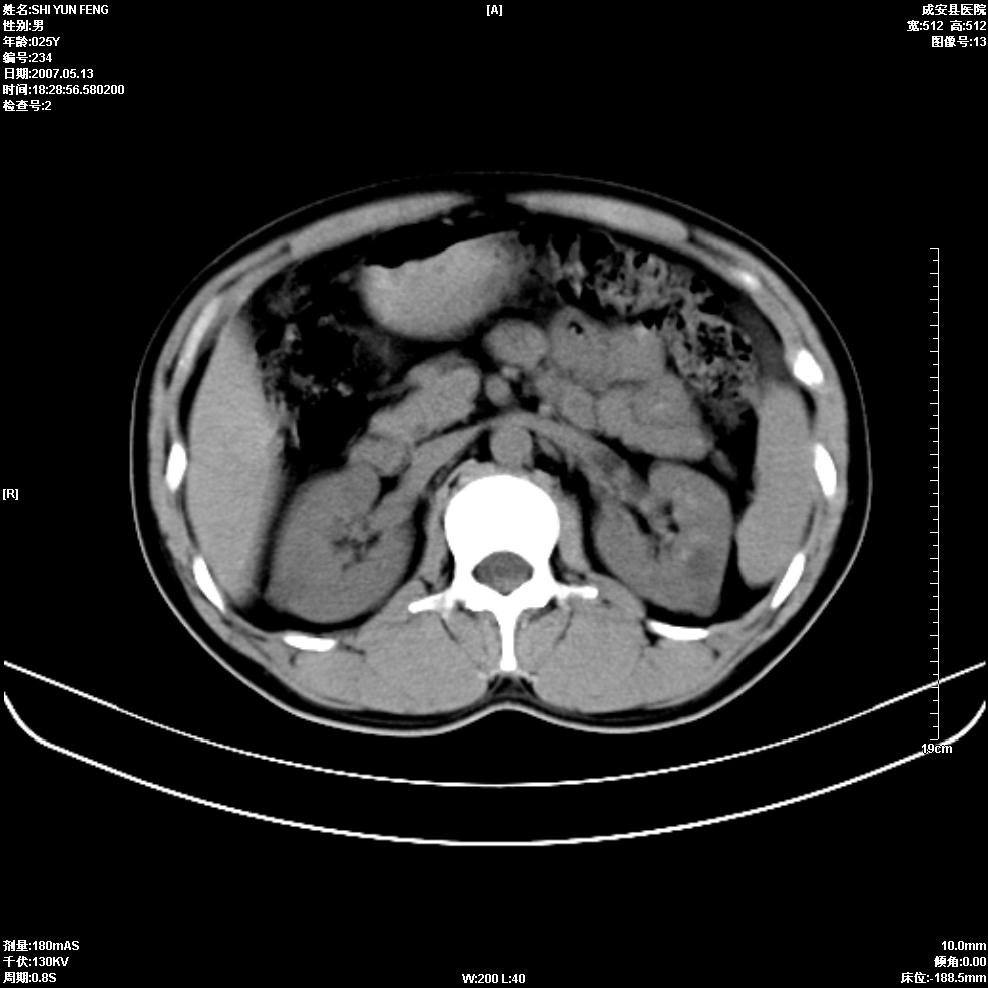

以下是引用zhangzhongshou在2007-5-16 7:36:00的发言:[br]多发性肾囊肿,左肾多发结石。不是多囊肾,楼主箭头所指多考虑左肾囊肿内结石或钙乳,髓质海绵肾不完全除外。[br][br][本贴已被 zhangzhongshou 于 2007-5-16 7:37:18 修改过][br][br][本贴已被 zhangzhongshou 于 2007-5-16 18:15:09 修改过]